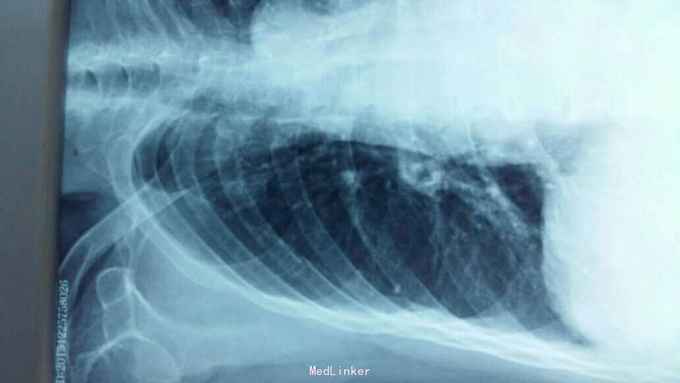

摔伤后胸痛、胸闷1天 1天前在自家劳动时摔伤胸部,伤后胸痛、胸闷,呼吸急促,活动后加重,不敢平卧,为诊治来院。

右侧胸部第4肋及第5胸肋关节处可触及骨摖感,触痛阳性。右肺呼吸音减弱。

1、右侧第4肋骨骨折;2、右侧第5胸肋关节脱位。 1、局部胸带外固定;2、促进骨愈合药物;3、平喘、化痰、预防感染;4、密切观察病情变化,随时复查。